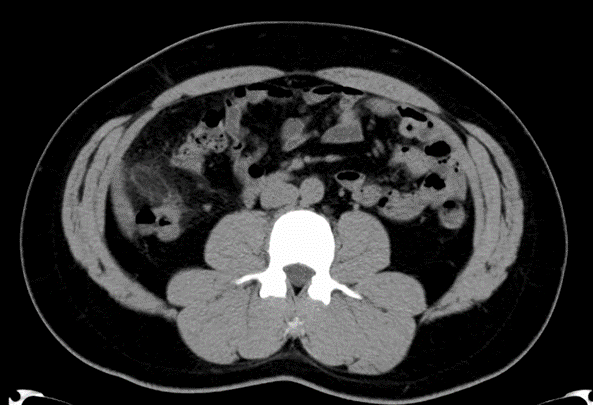

- 画像検査が重要::超音波(エコー)やCT検査で特徴的な所見(脂肪の腫瘤など)を確認する。

上行結腸壁から卵円形型の構造物が突出していて、内部の脂肪織濃度が上昇している。

※腹膜垂:直腸を除く大腸全域にあり、結腸の自由紐と大網紐に沿って垂れ下がっているメロンの種くらいの大きさの脂肪組織。